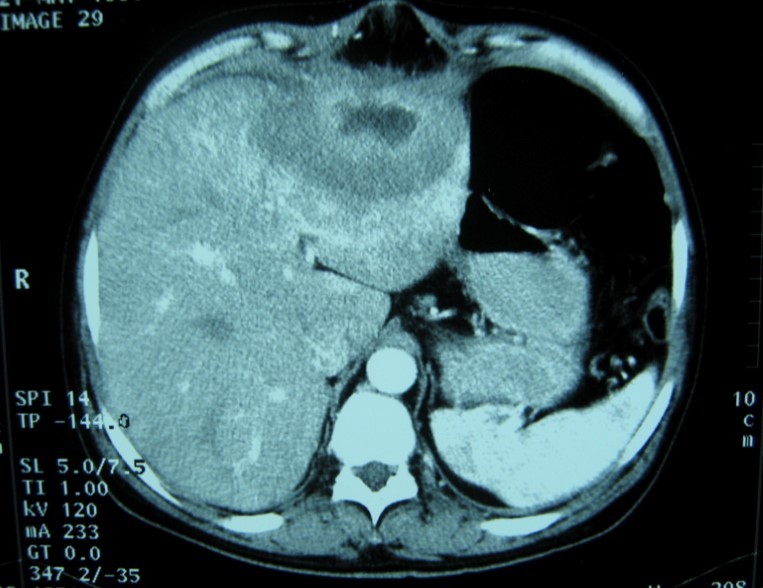

Laboratory analysis showed hemoglobin, 10.9 g/dL; white blood cell count, 9,800 cells/mm3, serum albumin, serum total bilirubin, alanine aminotransferase, aspartate aminotransferase, prothrombin time, hepatitis B surface antigen, and antibodies to hepatitis C, serum alpha-fetoprotein (AFP), carcinoembryonic antigen and carbohydrate antigen 19-9 (CA 19-9) were within normal range. Blood cultures were negative. Chest x-ray was normal. Ultrasound of abdomen showed a 10 cm hypoechogenic lesion in left liver (Figure 1). An abdominal CT showed a well-defined heterogeneous mass situated in his left hepatic lobe measuring 10 cm × 7 cm (Figure 2, Figure 3). The lesion featured central necrosis, a hyper-dense rim and a mild enrichment from the arterial phase in the CT, The diagnosis of primary hepatic tumor was suspected. An ultrasonography-guided needle biopsy of the liver was scheduled in order to rule out malignancy and to have a complete diagnosis. Cytology demonstrated a tuberculosis granuloma, acid-fast bacilli culture was positive (Figure 4). Anti-tuberculous therapy including isoniazid, rifampin, ethambutol, and pyrazinamide were prescribed. The patient completed the 6-month course of medication with success. The patient’s appetite and body weight were restored to previous levels. One year after the completion of treatment, the patient remained completely asymptomatic with disease free.

Figure 2.Abdominal computed tomography with intravenous contrast showing 10x7 cm low-density focal lesion

Computed tomography (CT) and magnetic resonance imaging (MRI) are helpful in diagnosis.

CT findings of tuberculosis abscesses can show low-density focal lesions with or without ring enhancement on contrast administration. These have also been seen in necrotic tumor such as hepatocellular, inflammatory disease and metastatic carcinoma 12.